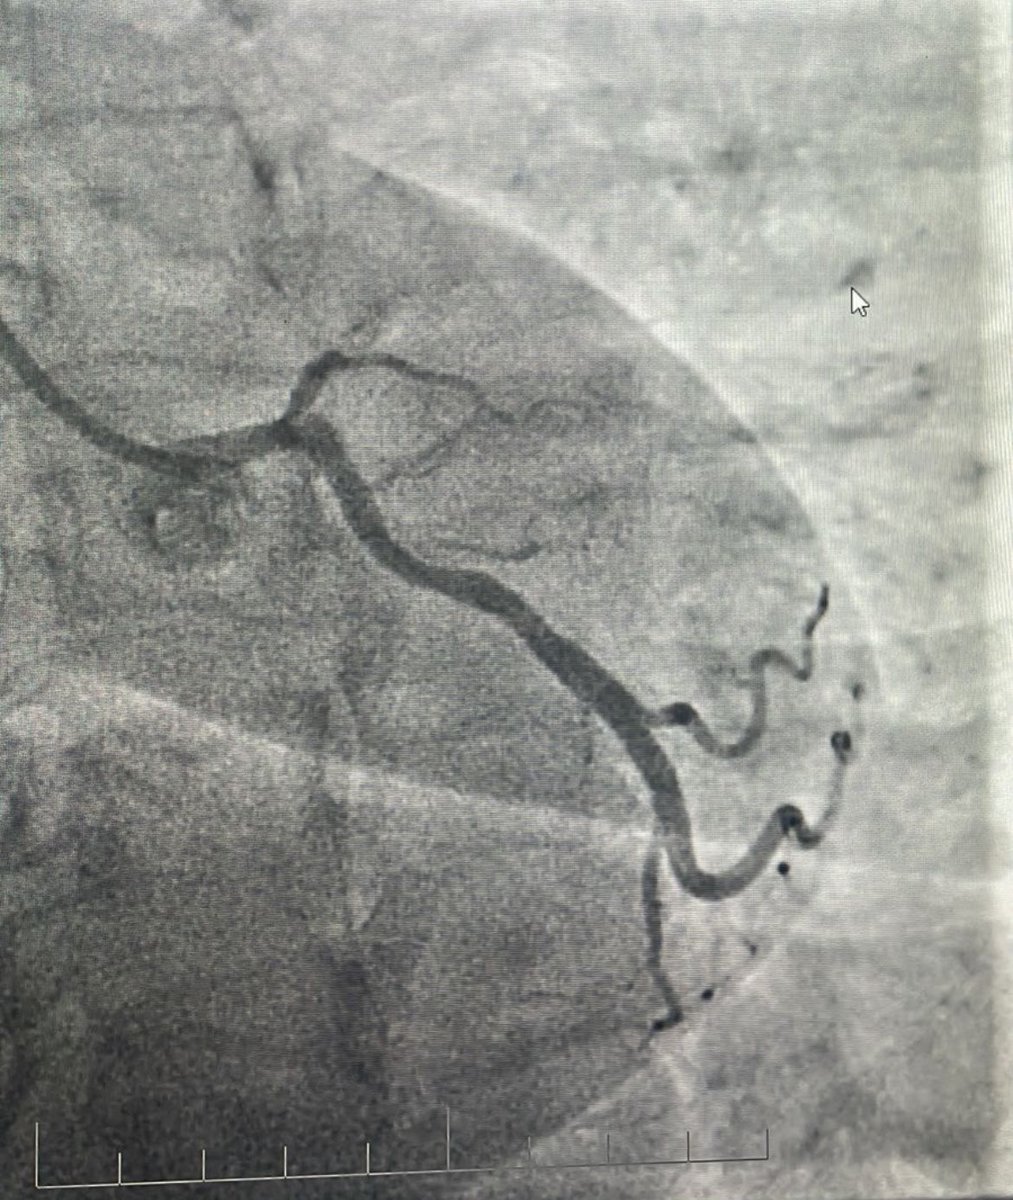

#Sharing is learning Diffusely diseased left system and #RCA #CTO. Cap looks ambiguous/blunt. How much should be done in this case? Pt was #symptomatic on GDMT. @DrIHHashmi1